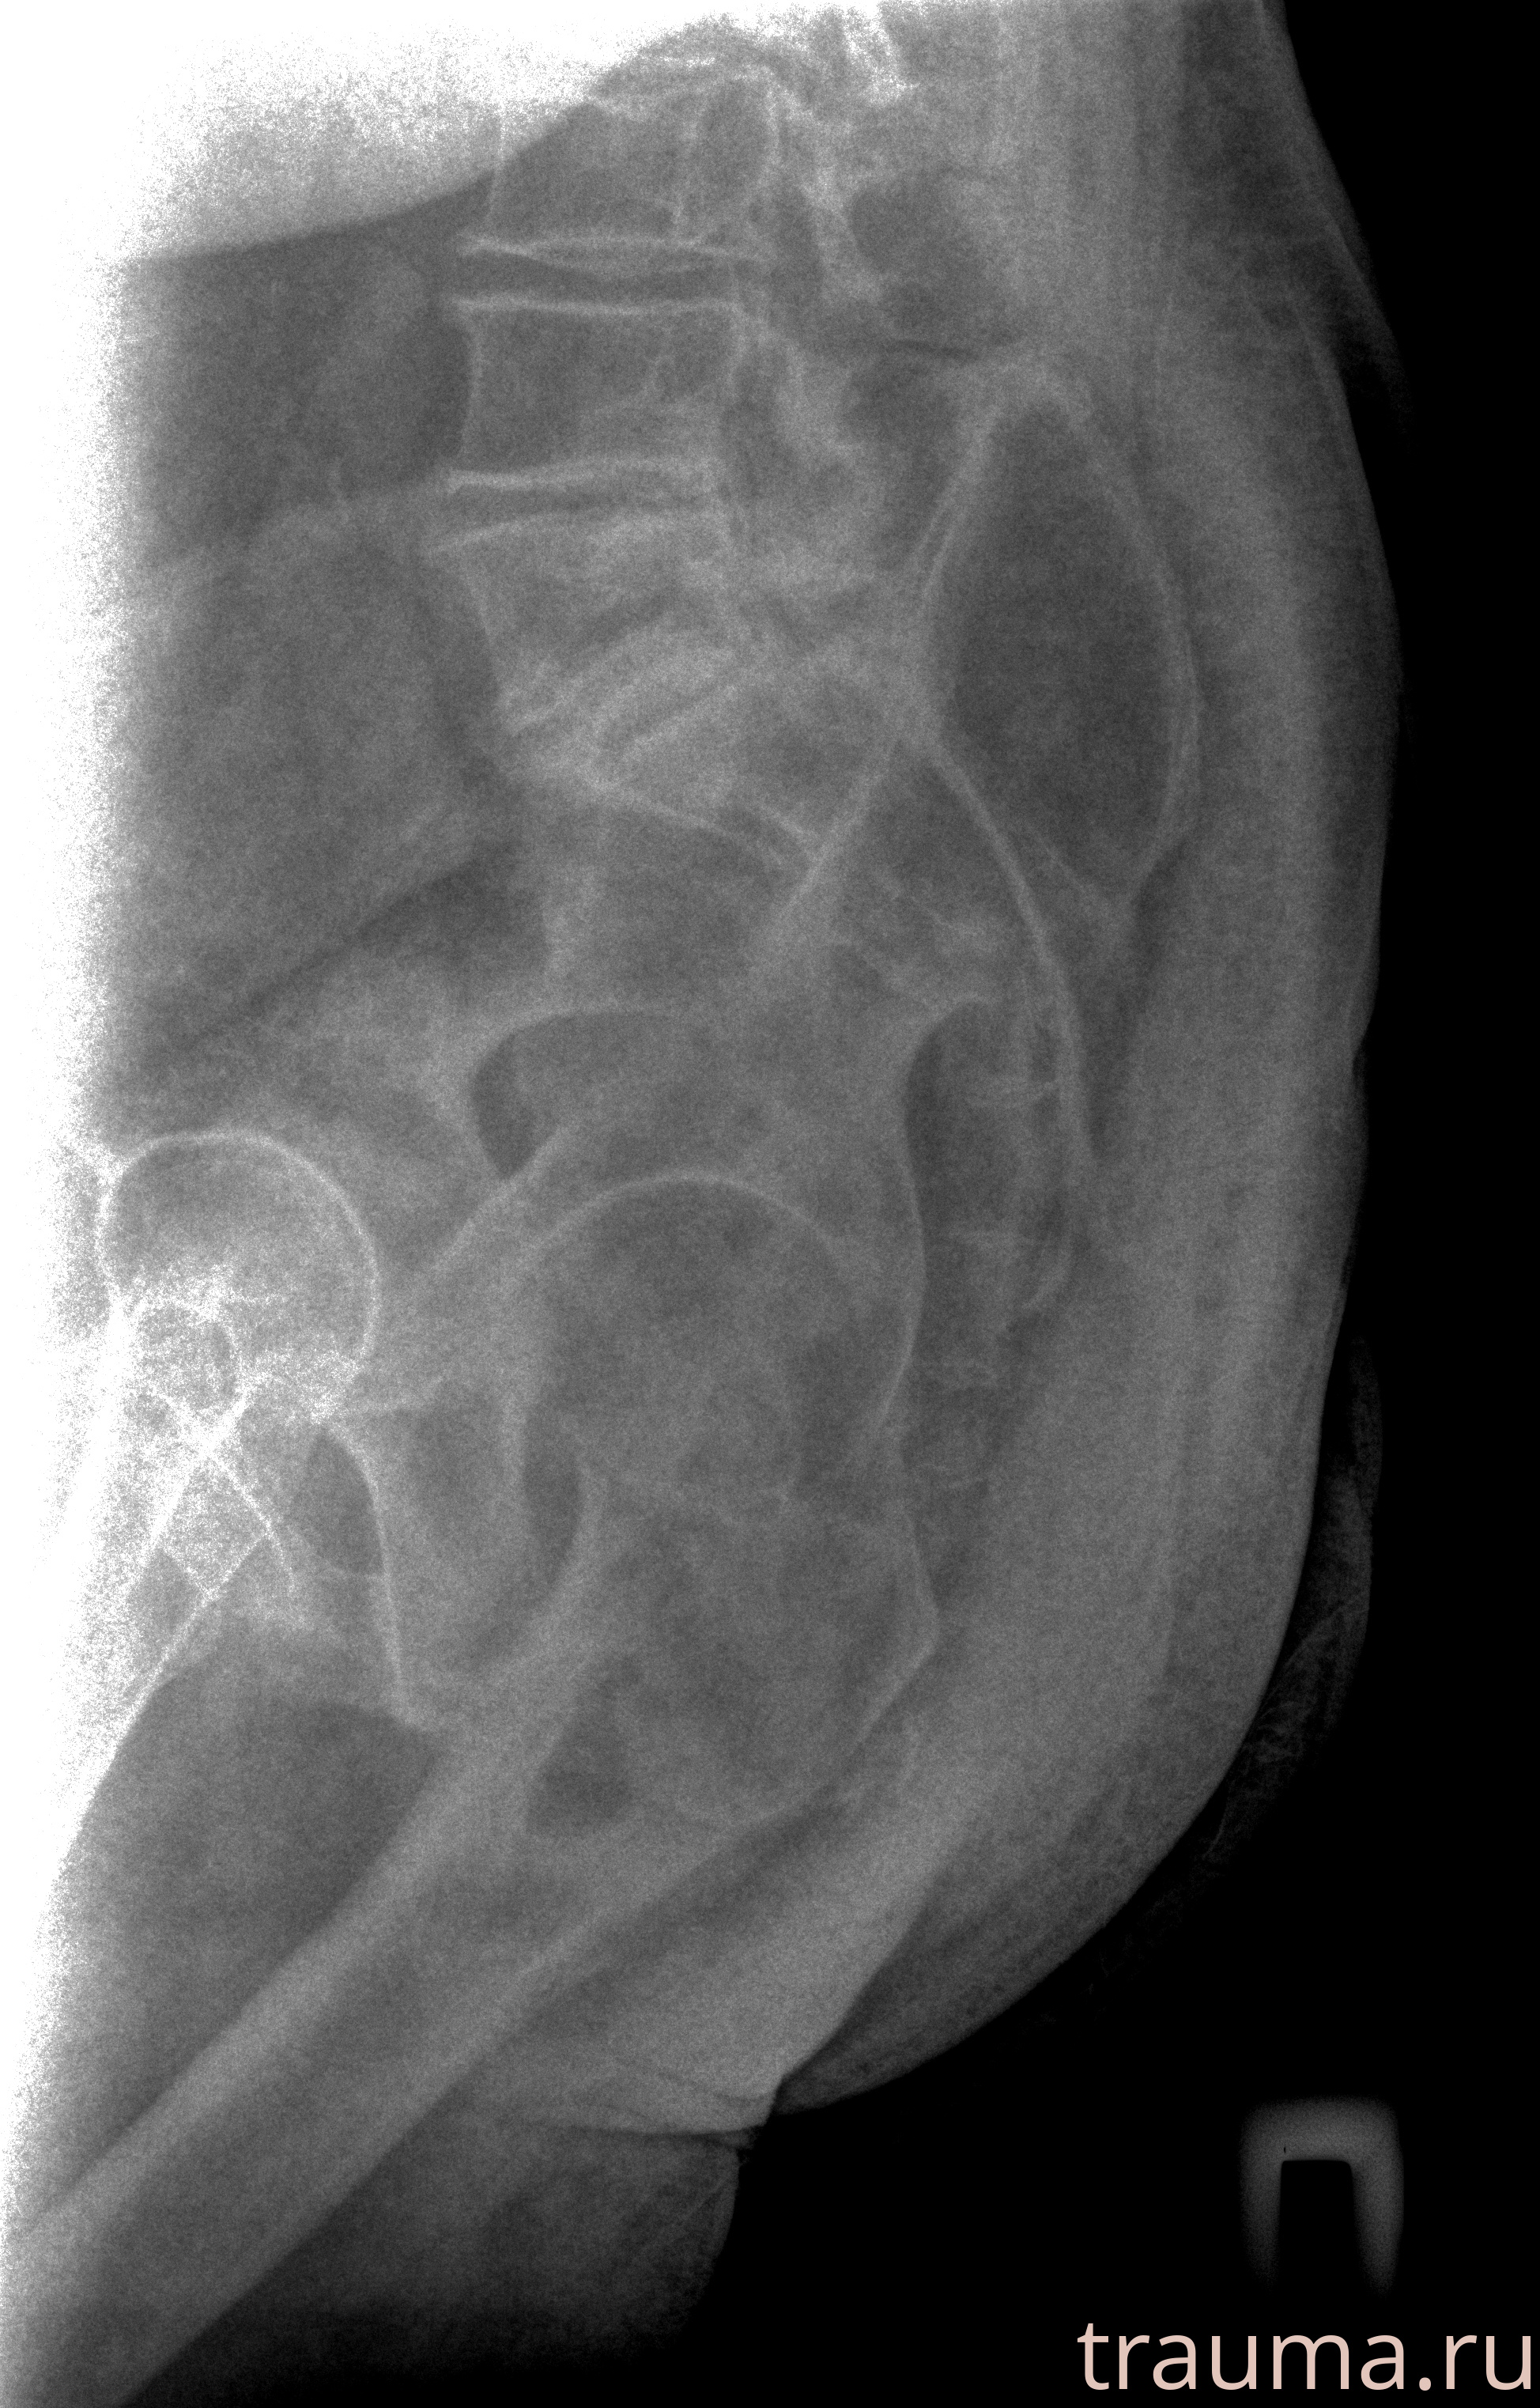

Рентген на дому: по вашему адресу приезжает врач-рентгенолог, травматолог-ортопед с мобильным рентгеновским аппаратом, проводит диагностику травмы или заболевания, делает необходимые рентгенограммы, дает рекомендации по дальнейшему лечению. Получить качественные снимки в домашних условиях возможно благодаря уникальной методике, разработанной МосРентген Центром для института  Склифосовского

при переломе шейки бедра и пневмонии от компании МосРентген Центр - партнера Института имени Склифосовского